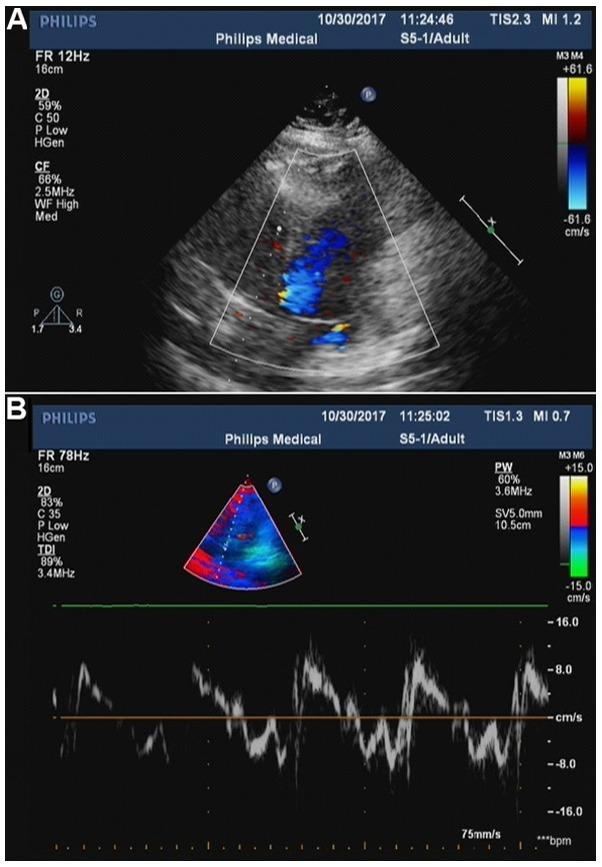

Acquired hemophilia A (AHA) is a rare antibody-mediated condition in which autoantibodies form against a coagulation factor, most commonly factor VIII (FVIII), causing severe coagulopathy. Here the present report presents a case of AHA in a 35-year-old postpartum woman with continuous polyserous bloody effusions who was admitted to the First Affiliated Hospital of Zhejiang Chinese Medical University (Hangzhou, China) in October 2017 without a history of trauma, anticoagulation treatment or coagulopathy. At presentation, the patient's hemoglobin level was low (70 g/l; normal range: 115-150 g/l) g/l, blood pressure was 89/58 mmHg (normal range, 90-140/60-90 mmHg), and activated partial thromboplastin time was 68.4 sec (normal range: 25.0-36.0 sec), with a normal international normalized ratio (0.94; normal range, 0.8-1.2). The reaction time in thrombography was prolonged (35.8 min; normal range: 5-10 min), coagulation FVIII had markedly decreased activity (12.6%; normal range, 60-150%), and FVIII inhibitor had a high titer [7.4 Bethesda units (BU)/ml; normal range, 0-0.6 BU/ml]. Notably, the patient's autoantibody level was markedly higher than normal (1:320; normal range: <1:100). The patient was successfully treated with bleeding control, eradication of FVIII inhibitor, and treatment of the underlying disease. To the best of our knowledge, this is the first case of AHA with polyserous bloody effusions in a patient with an autoimmune disorder during the postpartum period. Reports of such rare cases will aid the characterization of disease pathogenesis, which may in turn lead to the recognition and timely treatment of this rare disorder.

获得性血友病A(AHA)是一种罕见的抗体介导疾病,其中自身抗体针对凝血因子形成,最常见的是因子VIII(FVIII),导致严重的凝血病。本文报告了一例2017年10月入住浙江中医药大学附属第一医院(中国杭州)的35岁产后妇女AHA病例,该患者有持续性多浆膜腔血性积液,无创伤、抗凝治疗或凝血病病史。就诊时,患者血红蛋白水平低(70 g/l;正常范围:115 - 150 g/l),血压为89/58 mmHg(正常范围,90 - 140/60 - 90 mmHg),活化部分凝血活酶时间为68.4秒(正常范围:25.0 - 36.0秒),国际标准化比值正常(0.94;正常范围,0.8 - 1.2)。血栓弹力图反应时间延长(35.8分钟;正常范围:5 - 10分钟),凝血因子FVIII活性显著降低(12.6%;正常范围,60 - 150%),FVIII抑制物滴度高[7.4贝塞斯达单位(BU)/ml;正常范围,0 - 0.6 BU/ml]。值得注意的是,患者自身抗体水平明显高于正常(1:320;正常范围:<1:100)。该患者通过控制出血、消除FVIII抑制物及治疗基础疾病获得成功治疗。据我们所知,这是产后自身免疫性疾病患者中首例伴有多浆膜腔血性积液的AHA病例。此类罕见病例的报告将有助于疾病发病机制的特征描述,这反过来可能有助于识别和及时治疗这种罕见疾病。